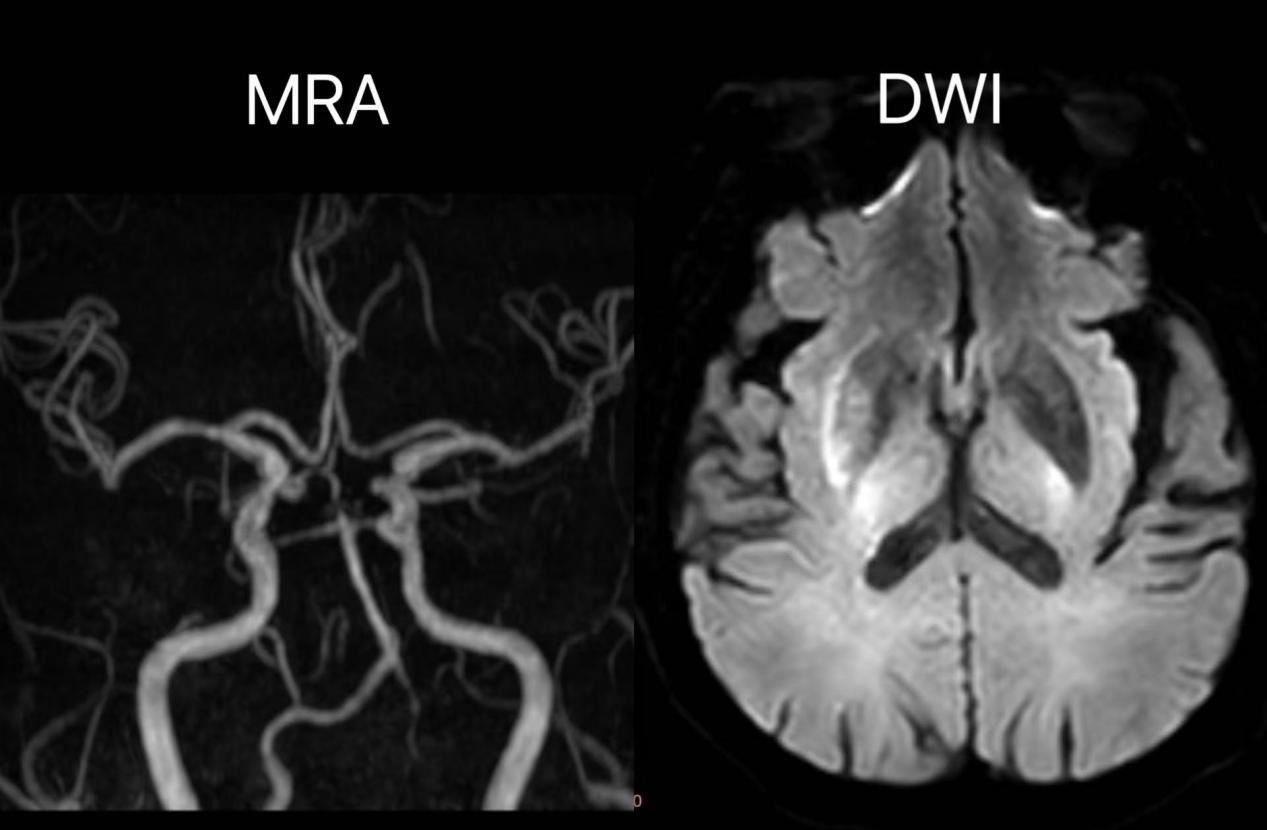

取栓前后造影结果对比

术后一天复查头颅MR示:右侧基底节区-放射冠少量斑片状急性期脑梗死灶;右侧大脑中动脉显影较前明显改善。

本例救治中,神经内科团队采用指南推荐的“桥接治疗”方案,一是静脉溶栓:快速溶解细小血栓,为脑组织争取生机;二是血管内机械取栓:针对大血管“堵点”,通过微导管精准取栓,立竿见影。

双技术联合应用,既避免瘫痪、失语等后遗症,更将血管再通率提升至90%以上,彰显我院在卒中超早期治疗中的硬核实力!